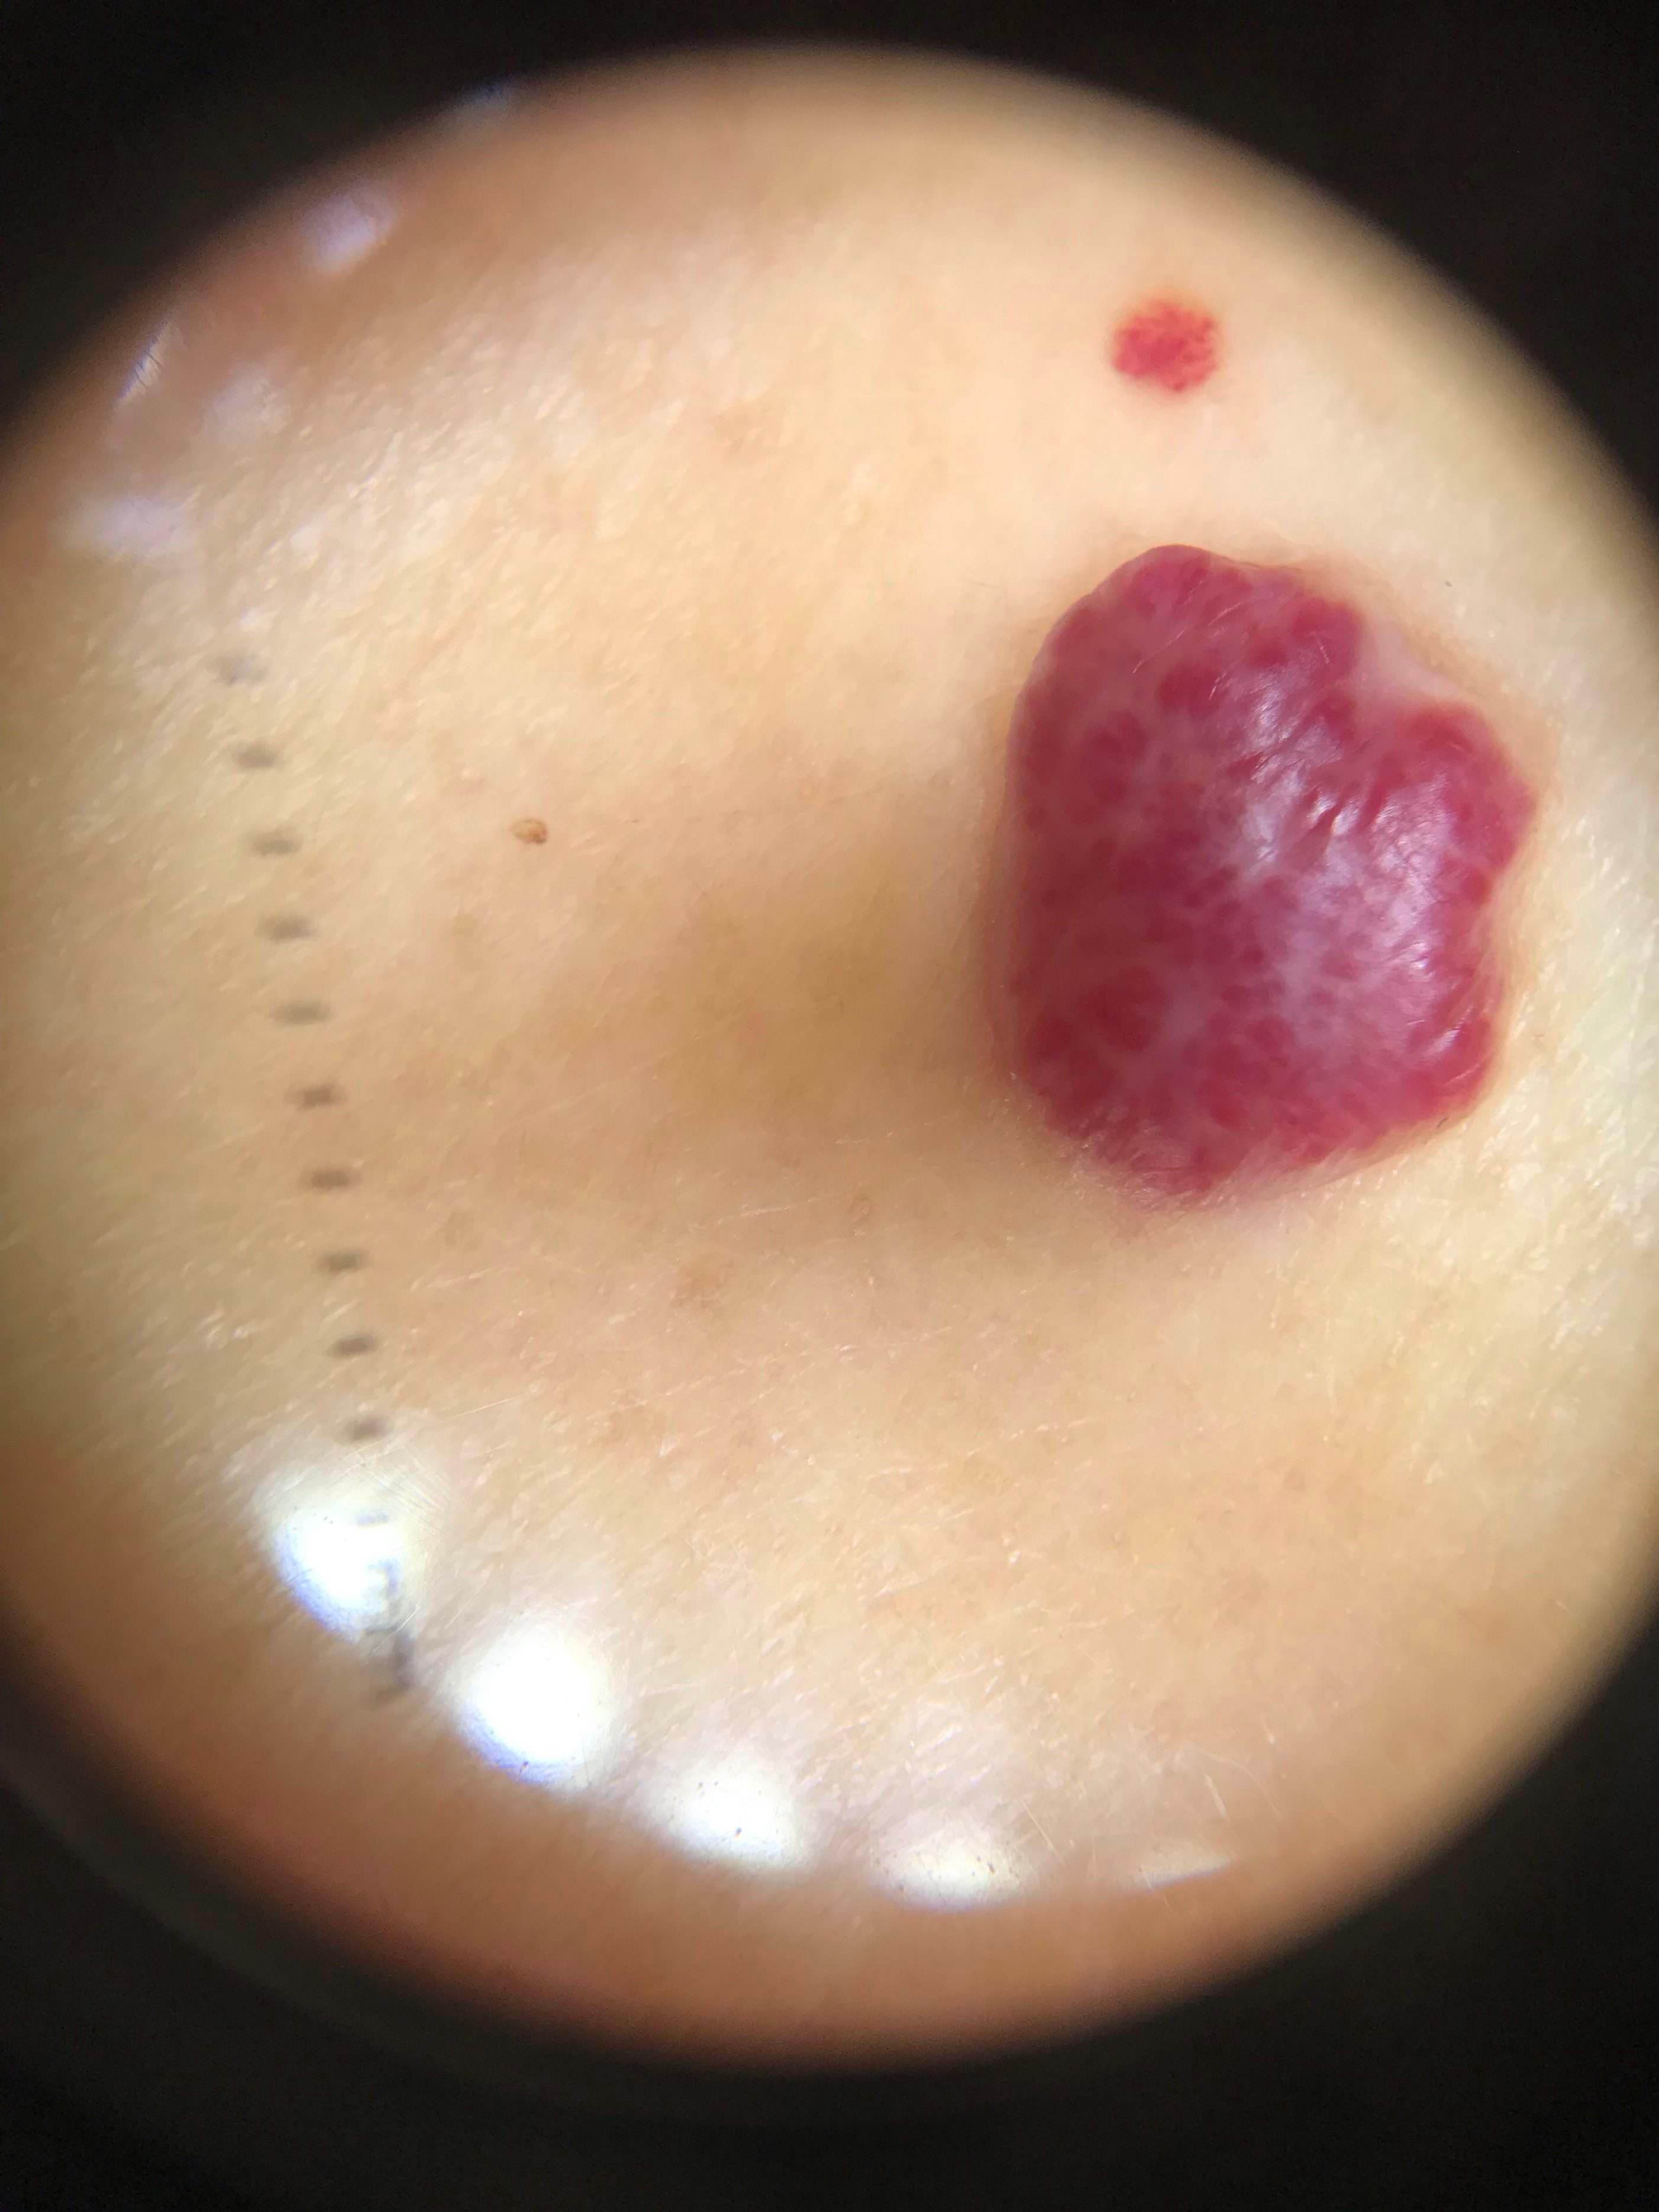

临床上,判断痣是否为恶性有ABCDE原则:

Asymmetry: 病灶不对称

Border: 边缘不规则

Color: 颜色不均一,如会在棕黄色或棕褐色基础上参杂粉红色、白色、蓝黑色或其他颜色

Diameter: 直径>6mm

Evolving: 有恶性进展,如出现上述在大小、形状、颜色方面的变化,此外会出现发痒、疼痛、溃疡、感染、出血等情况,或出现卫星结节(在痣的边上出现新的小痣)。

皮肤镜检查就先进得多,它的工作原理类似于“放大镜”,适用于人眼难以鉴别的皮肤肿瘤,检出率高,如色素痣的良恶性,基底细胞癌等,并且还是无创的。